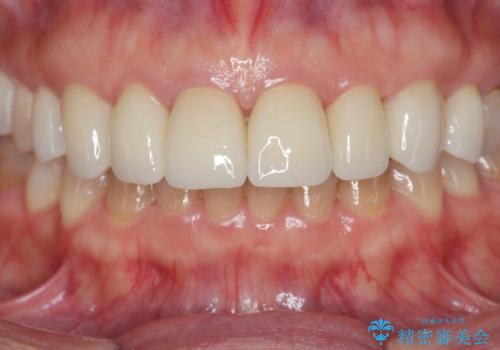

- 88万円(仮歯・ジルコニアクラウン×8)費用は治療当時の料金となります

ラミネートよりもより透明感の再現性の高いジルコニアクラウンの出来に喜んでいただくことが出来ました。